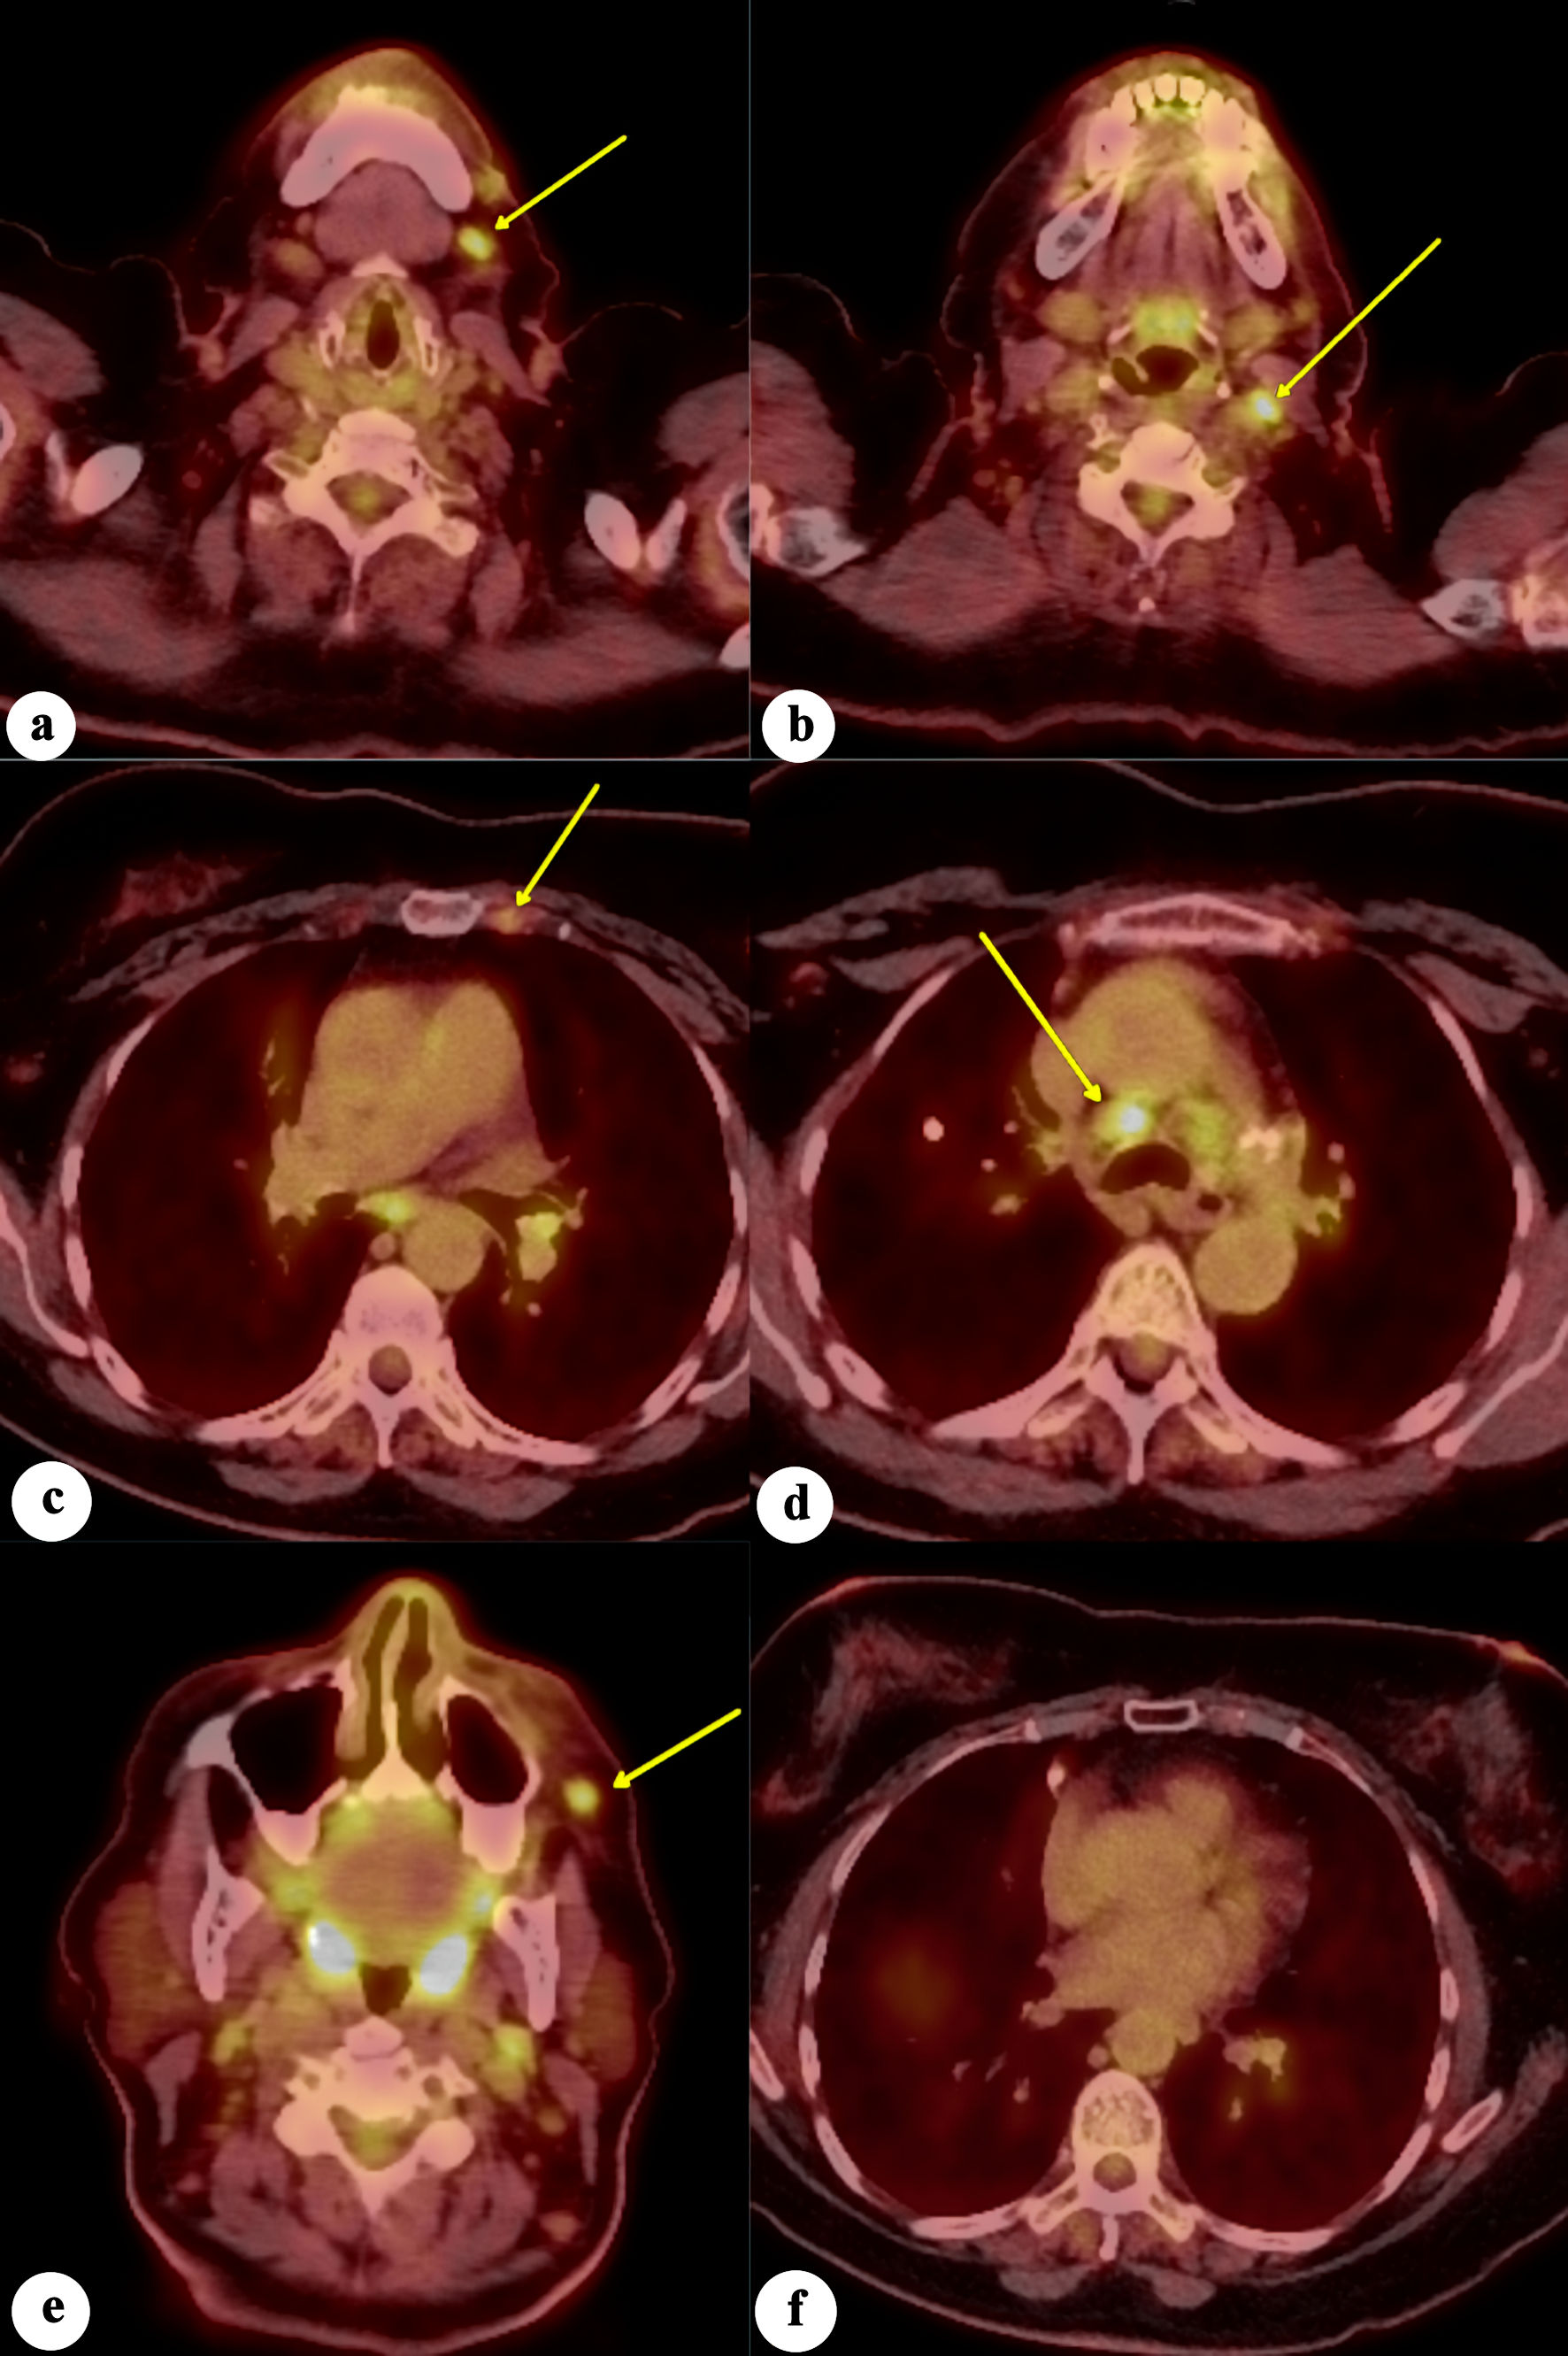

The positron emission tomography/computed tomography (PET/CT) showed tracer-avid left anterior cervical, left internal mammary arterial chain, and pulmonary mediastinal/hilar lymphadenopathy, suggestive of metastatic disease. Additionally, a 6-mm tracer-avid nodule with maximum standardized uptake value (SUVmax) of 4.6, located within the left anterior facial soft tissues adjacent to the zygomatic bone, raised concern for neoplastic involvement. There was no evidence of a tracer-avid primary malignant neoplasm in the breast, pharyngeal, glottic, lung, abdominal, or pelvic organs (Fig. 8). The patient denied any family history of breast cancer. In the absence of a prior history of breast cancer or a suspicious breast lesion clinically, a primary cutaneous carcinoma with mammary phenotype, specifically eccrine carcinoma, was suggested. Due to the R2 resection, the patient was initially offered treatment with cisplatin as a radiation sensitizer followed by radiotherapy. She fully understood the prognosis, as well as the benefits and risks associated with the treatment options, but ultimately declined chemotherapy and radiotherapy. She came to our hospital for a second opinion and commenced treatment with letrozole and ribociclib, a regimen extrapolated from receptor-positive breast cancer therapy. The patient has been on letrozole and ribociclib for 10 months. She developed a rash on her arms and legs, and mild leukopenia with a white blood cell count of 2.9 × 103/µL, which resolved 2 months later. Otherwise, she tolerates the treatment well without signs of disease progression. The follow-up PET/CT after 6 months revealed decreased left facial subcutaneous nodule adjacent to the zygomatic bone, measuring 5 × 3 mm with an SUVmax of 1.5. There was resolution of abnormal tracer uptake in the left internal mammary arterial chain lymph node, with stable tracer uptake of mediastinal lymph nodes.

Click for large image

Figure 8. Fluorodeoxyglucose positron emission tomography/computed tomography (FDG-PET/CT) scan of the whole body demonstrates increased FDG avidity in (a) left level 1 lymph node, (b) left level 2 lymph node, (c) left internal mammary lymph node, (d) mediastinal/paratracheal lymph node, and (e) left malar soft-tissue nodule (yellow arrows), concerning for metastatic disease. (f) No evidence of increased FDG avidity within the breast tissues to suggest neoplastic disease.